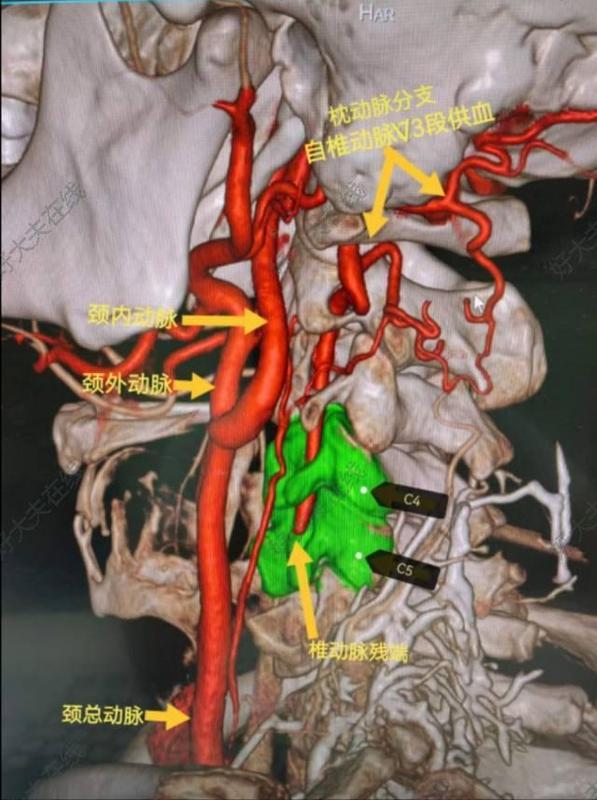

治療前患者男性,41歲,既往高血壓、高脂血癥病史,有吸煙及飲酒史?;颊?月前出現(xiàn)枕葉和小腦梗塞,1月前在當?shù)匦蠨SA發(fā)現(xiàn)左側椎動脈V1-V2(至C5水平)閉塞,枕動脈肌支自V3供血,并向近心端返流至C5水平,呈震蕩血流,考慮梗塞是由于震蕩血流造成椎動脈內斑塊脫落引起,患者存在罕見的椎動脈殘腔綜合征(VertebralArteryStumpSyndrome,VASS),這是后循環(huán)缺血性卒中的少見原因。治療中治療方案:因椎動脈起始端閉塞過長,故設計手術方案為頸外動脈-橈動脈-椎動脈搭橋(ECA-RA-VAbypass),術中行腦氧、TCD和電生理監(jiān)護等多模態(tài)監(jiān)護。該患者情況因為既往放置主動脈內覆膜支架無法行介入微創(chuàng)治療。治療后治療后1年術后腦灌注CT對比術前改善,術后患者訴視物光線較術前明亮清晰,術后一年復查搭橋血管通暢良好。